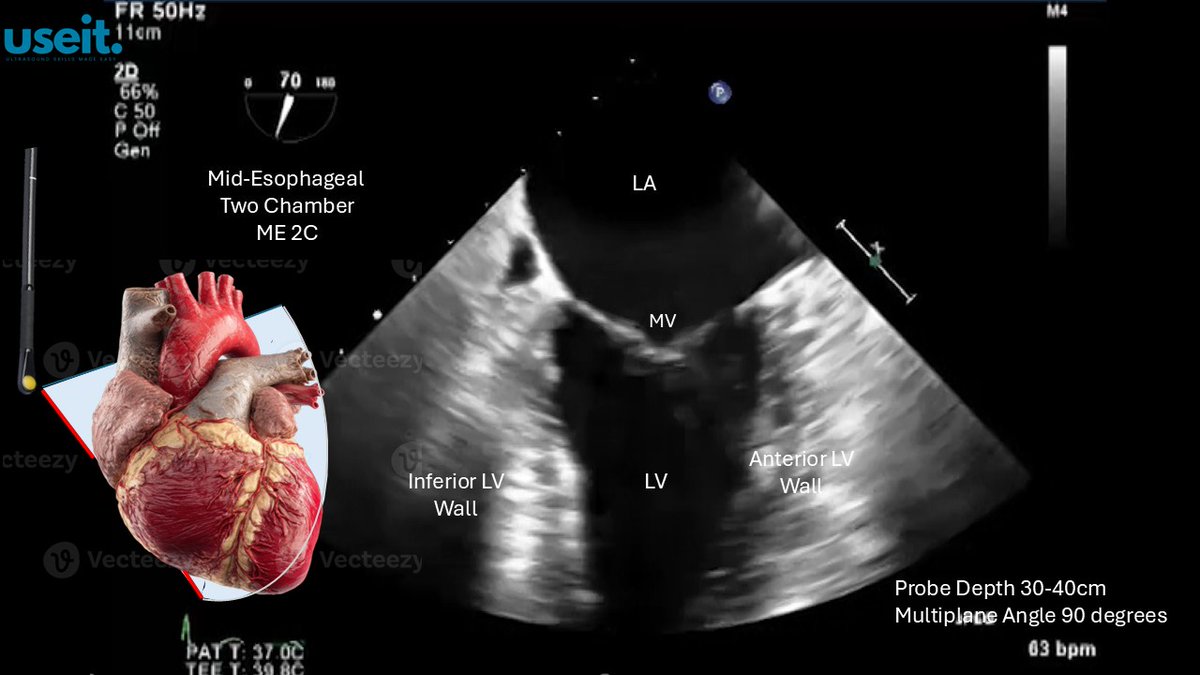

#TEE #useit ME2C View

pocus_today's tweet image. #TEE #useit

ME2C View